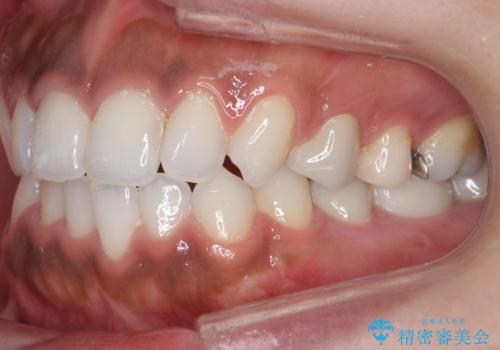

奥歯の高さがない 20代で入れ歯もインプラントも難しい ブリッジで歯を残す治療

虫歯を放置したため、左下奥歯の上下の歯の隙間が全くなく入れ歯もインプラントも難しい状態でした。

左下6番は残根状態だったため、やむなく抜歯を行い、⑤6⑦ブリッジとしました。

歯周外科手術を併用し、骨の高さを調整して歯の高さをしっかり出す手術(クラウンレングスニング)も行いました。